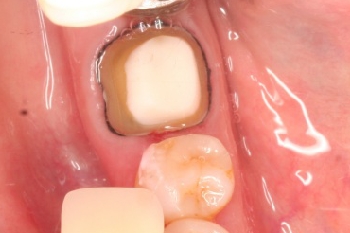

千葉市中央区 K.C様 右下6番 メタルボンドクラウン修復

担当歯科医師:丸林浩太郎